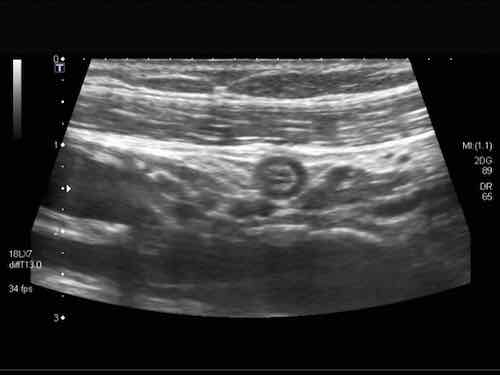

Intussusception

Đây là hình ảnh siêu âm của một trẻ 2 tuổi bị lồng ruột hồi manh tràng từng đợt, được khám trong khoảng thời gian giữa các cơn.

Hồi tràng với nhiều mảng Peyer sa vào manh tràng.

Hình ảnh siêu âm kinh điển của lồng ruột hồi-manh tràng ở hai trẻ khác nhau.

Trong cả hai trường hợp, đoạn hồi tràng bị lồng được định vị không đối xứng bên trong ống lồng ngoài, do mạc treo ruột tăng âm có chứa mỡ, bám vào hồi tràng và đi theo hồi tràng khi bị kéo vào trong.

Trong mạc treo, siêu âm cho thấy một hạch bạch huyết mạc treo (hbh) phóng đại ở cả hai.

Các hạch này phì đại như một phần của tình trạng tăng sản hạch bạch huyết toàn thân và khônghu trú trong lòng hồi tràng.

Do đó đây không phải là điểm dẫn đầu nguyên phát. Ở bệnh nhân bên phải, ruột thừa (mũi tên) cũng bị kéo vào trong.

Lưu ý cấu trúc đa lớp của thành bụng phía trước của phức hợp lồng ruột, đại diện cho ba lớp thành ruột bị gấp lại.